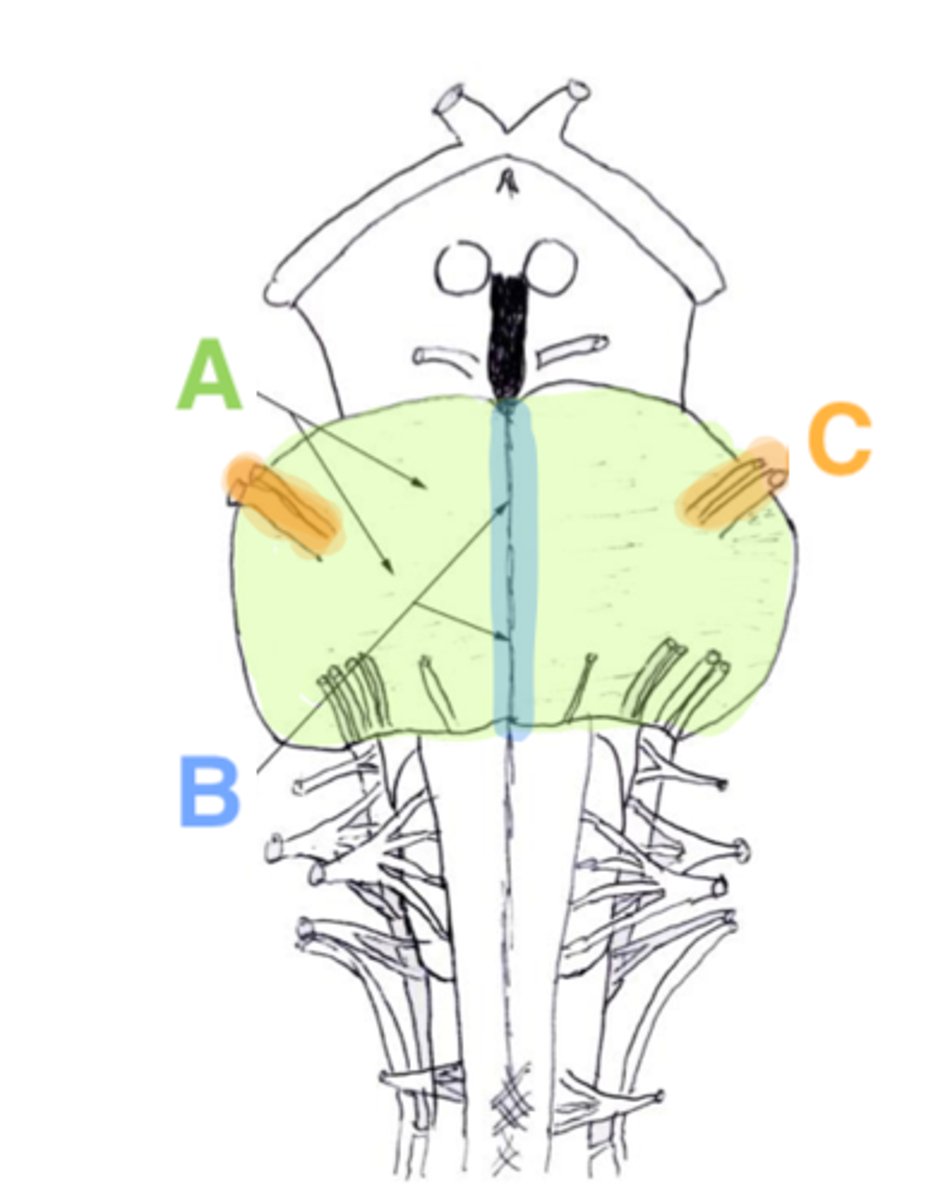

refers to the large round protuberance on the ventral pons that represents a "bridge" of horizontally oriented fibers connecting the right and left sides

basilar portion

longitudinal midline groove of the pons that is the superior continuation of the ventral median sulcus/fissure, containing a namesake artery

basilar sulcus

white matter stalks that connect the pons to the cerebellum

middle cerebellar peduncles

What is the only cranial nerve that attaches to the pons?

CN V

portion of the pons that is dorsal to the basilar portion and represents mostly longitudinally oriented fibers and cranial nerve nuclei

**also helps to form the floor of the 4th ventricle

tegmentum

A

basilar portion

B

basilar sulcus

C

CN V

B

middle cerebellar peduncles

tegmentum